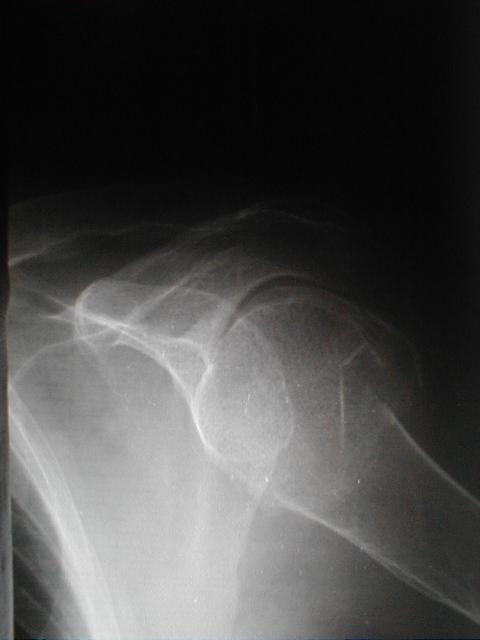

症例1

上腕骨頚部(外科)骨折と肩関節脱臼の合併症例

66歳 女性

左上腕骨頚部(外転)骨折

左肩関節脱臼